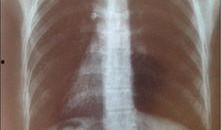

滕州最新爆料消息疫情情况,多区域现新增病例,防控措施持续升级

最近滕州的小伙伴们是不是都在密切关注着当地的疫情动态呢?这不,刚刚又有最新爆料消息传来,让我们一起来看看吧!滕州疫情最新动态话说...